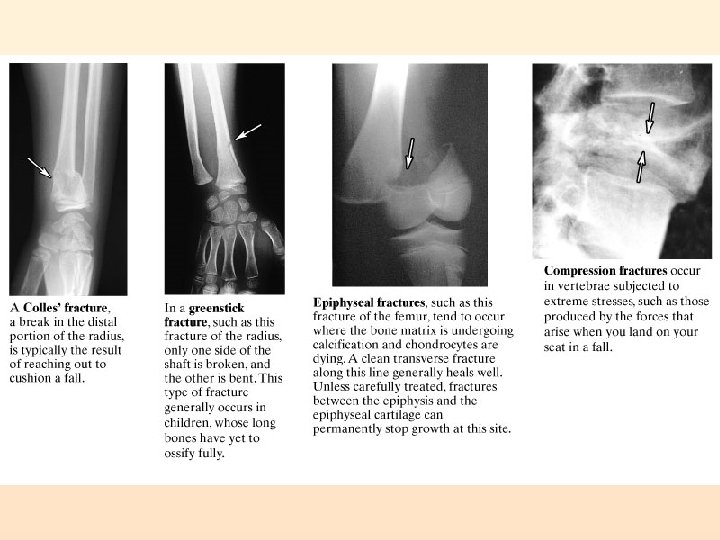

Fractures Simple (Closed): Compound (Open):